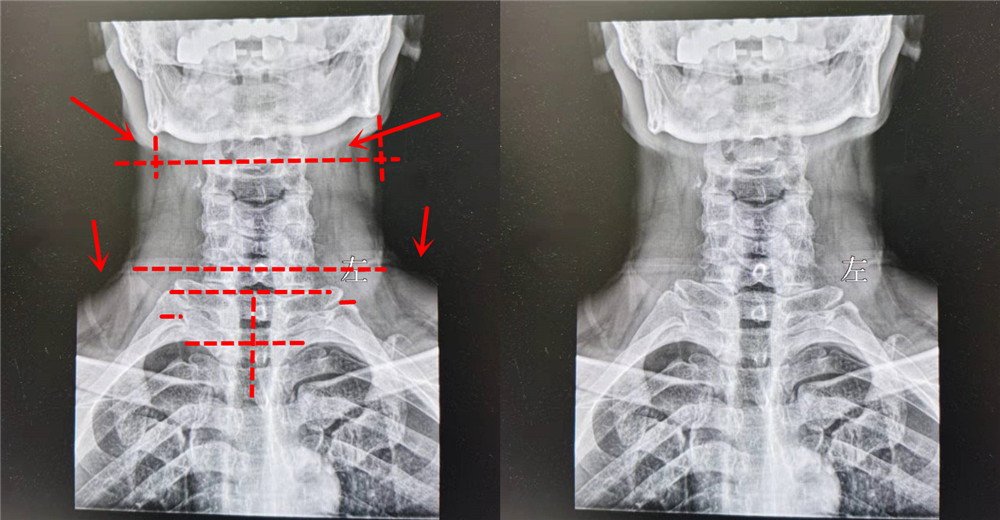

病人:29岁 , 诊断出颈源性高血压患者

看这两张片子 , 大家能看出点什么来?可能不仔细看 , 大家感觉 , 其实没有什么毛病呀!大家应该听过一句话 , 失之毫厘谬以千里!身体关节部位一丁点的变动 , 其实都是有可能影响你身体的真凶!就比如现在这个患者 , 年龄并不大 , 但是家里环境并不是太好 , 又感觉自己是青壮年 , 所以是以工作为主 , 生活很没有规律 , 再加上长期的抽烟喝酒 , 业务陪客户 , 所以年纪轻轻就高血压!

后来就有一位医生提出来 , 比如 , 颈源性高血压患者 , 如果将患者的各个颈椎骨矫正 , 就是通过正骨的方式将骨骼矫形好 , 然后通过针灸调理局部肌肉经脉 , 通过推针刺激穴位 , 通过中药内服 , 中药外敷熏蒸能不能将颈椎局部调理好!